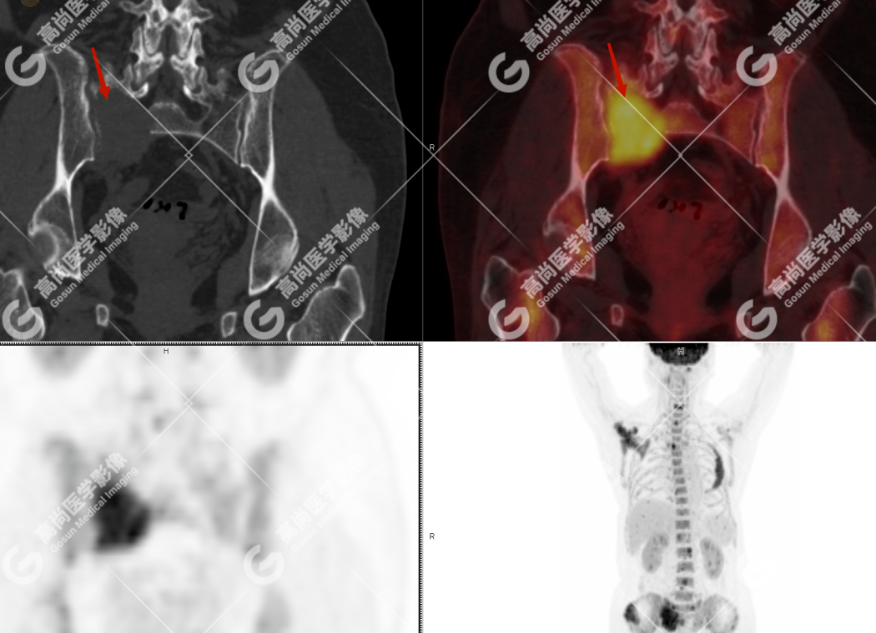

颅骨、寰椎前弓左侧份、第 6 颈椎、双侧肩胛骨(右侧为著)、左侧第 4 肋骨、第 1 胸椎、第 4 胸椎、第 2 腰椎及附件、第 4 腰椎及附件、骶骨、右侧髂骨、左侧坐骨结节、左侧股骨颈、双侧股骨小转子等均不同程度骨质吸收、破坏,其中右侧肩胛骨、左侧第 4 肋骨及骶骨右侧份软组织肿块影形成,上述病变均考虑恶性肿瘤(血液系统来源,多发骨髓瘤可能性大),建议右侧髂骨翼穿刺活检明确。

(4)PET-CT 影像表现:在溶骨性破坏区出现相重叠的 18F- FDG 高代谢区;通常呈弥漫性高代谢区。